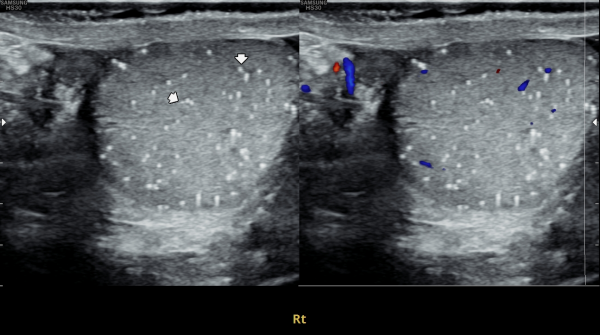

서울가정의학과의원에 첫 내원 당일 지난 5개월동안 회음부 통증과 배뇨장애로 타 비뇨기과 여러곳에서 치료를 했으나 증상의 호전이 없다고 내원 당일 검사한 경직장 전립선 초음파 검사상 사정관 입구의 석회화와 사정관의 섬유화 그리고 정낭의 낭종이 관찰되는 초음파 자료입니다.

On the first visit to Seoul Family Medicine Clinic, the patient reported having perineal pain and urination problems for the past five months, despite receiving treatment at several other urology clinics with no improvement.

A transrectal prostate ultrasound performed on the day of the visit showed calcification at the opening of the ejaculatory duct, fibrosis (scarring) of the duct itself, and cysts in the seminal vesicles.

또한 방광벽이 배뇨장애로 두꺼워져 과민성 방광이 의심되는 초음파 사진입니다.

The ultrasound image also shows that the bladder wall has become thickened, likely due to urination difficulties. This may suggest an overactive bladder, which can cause frequent or urgent urination.